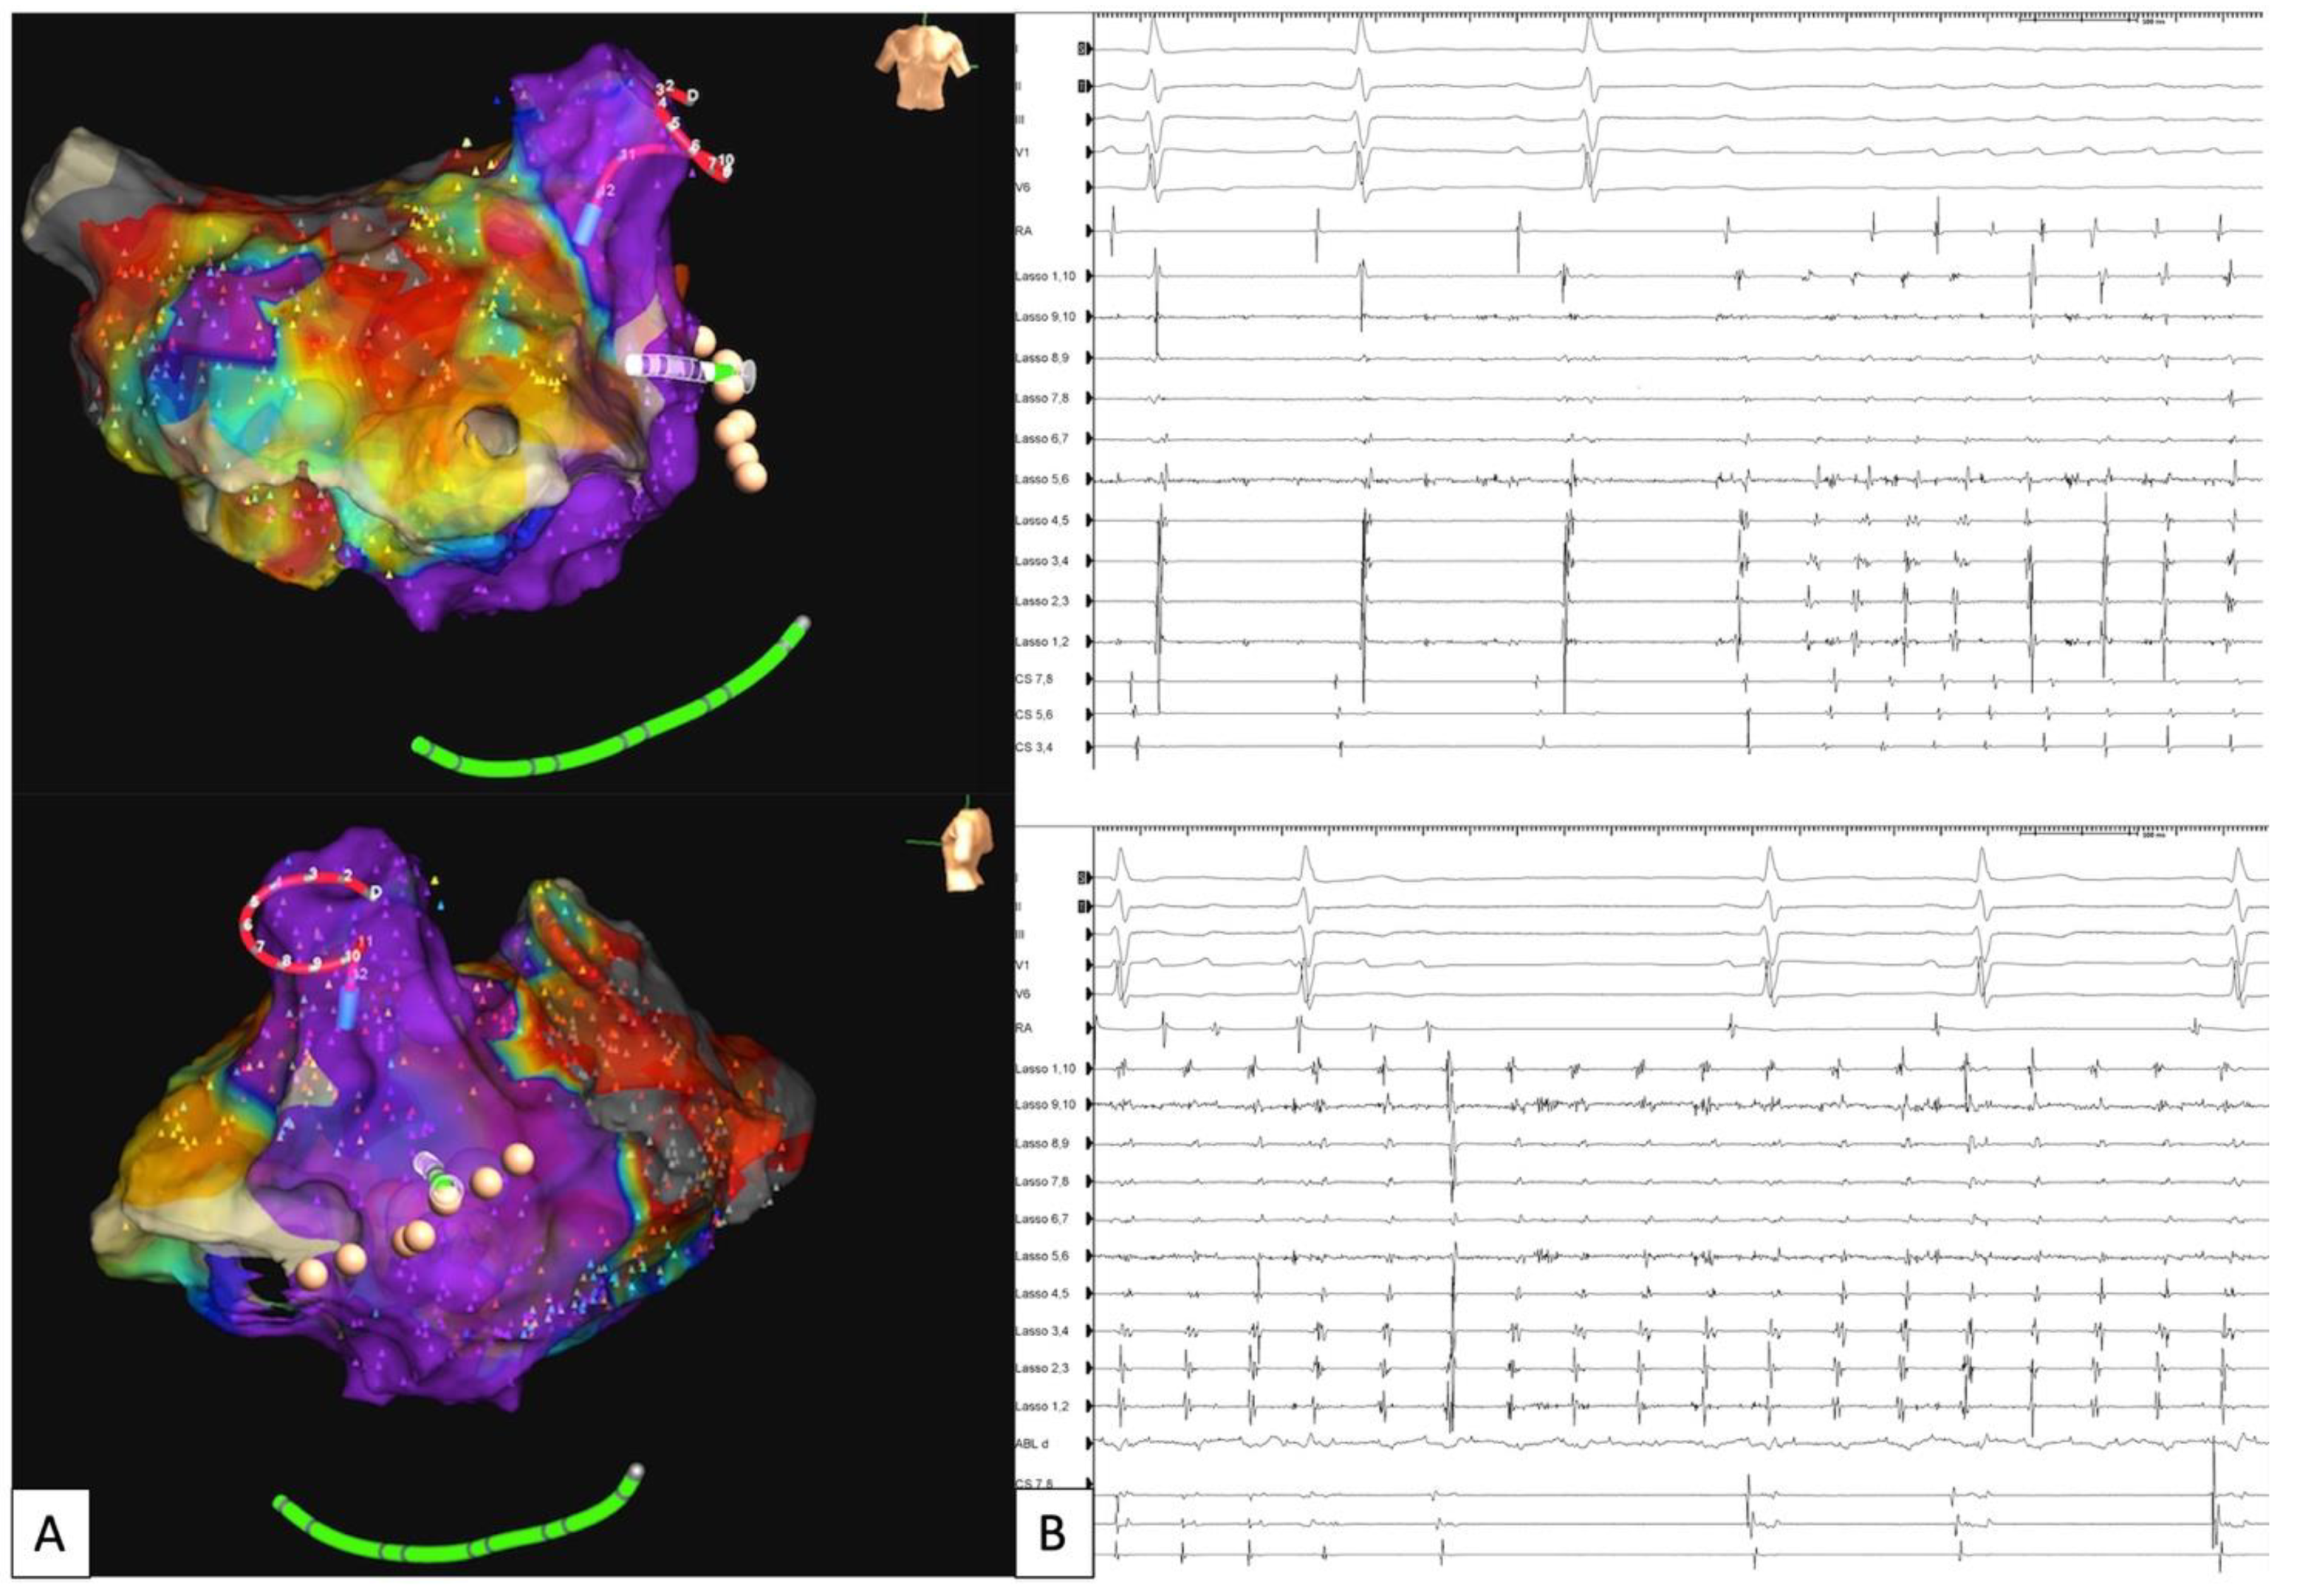

- Madaffari, A.; Knecht, S.; Spies, F.; Schaer, B.; Kühne, M.; Sticherling, C.; Osswald, S. Epicardial Connection: The Achilles Heel of Gap Mapping After Wide Antral Pulmonary Veins Isolation. JACC Clin. Electrophysiol. 2019, 5, 1356–1357. [Google Scholar] [CrossRef] [PubMed]